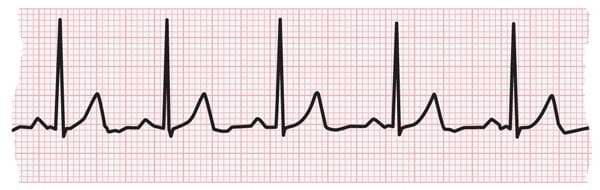

El electrocardiograma (ECG) mide la actividad eléctrica del latido de corazón. Con cada latido, una onda eléctrica se desplaza por el corazón. Esta onda hace que el músculo se comprima y bombee sangre desde el corazón. En el caso de un latido de corazón normal, un ECG muestra la frecuencia y el ritmo de las contracciones de las cavidades superiores e inferiores del corazón.

Tira de ECG que muestra un latido de corazón normal